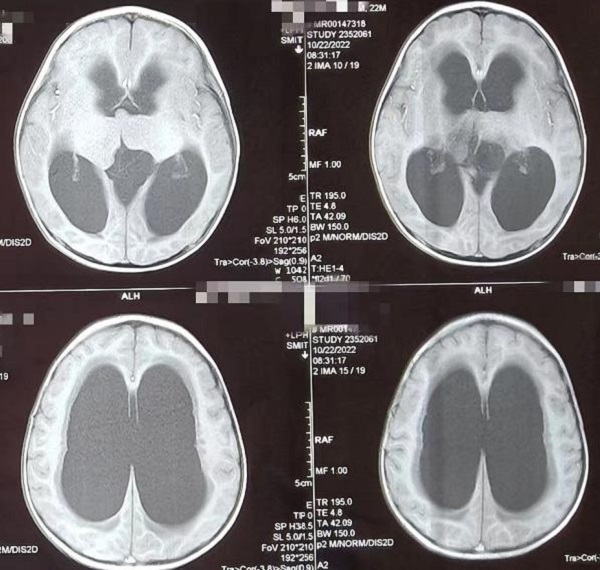

一岁多的赫赫小朋友自出生头颅就比同龄小孩大,近半月来进食后出现呕吐,伴头痛,在当地医院及省内多家医院治疗不见好转,于是来到陕健医二一五医院神经重症监护室,因患儿近半月多不能正常进食,入院时精神萎靡,头颅MRI检查提示“脑室系统扩大,双侧脑室额角周围间质水肿,左侧丘脑占位病变,鞍上池及小脑上池扩大”。

为进一步鉴别脑积水类型,行磁共振3D FIESTA序列检查可见侧脑室扩大明显,中脑导水管中段阻塞、三脑室底受压下陷,诊断梗阻性脑积水。